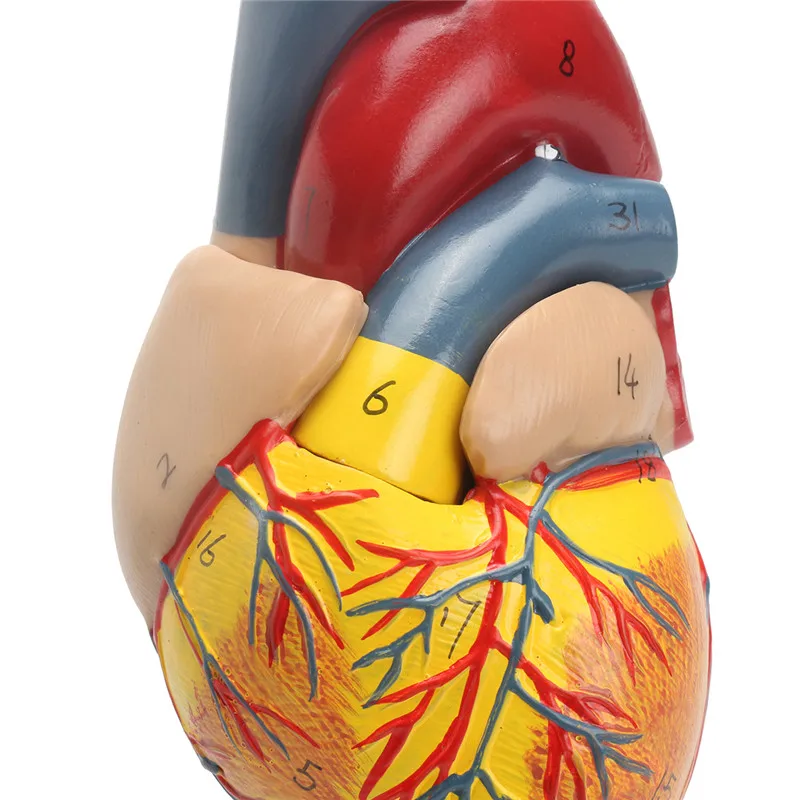

Фотографии и 3D-модели анатомии сердца человека